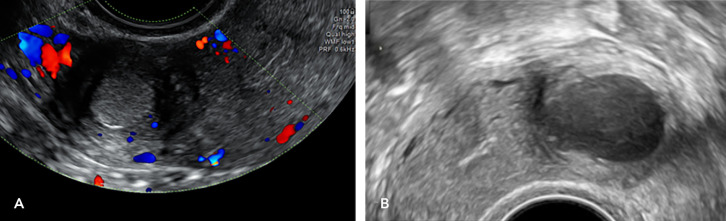

Results: Patients with ACUM present with typical symptoms such as dysmenorrhea and dyspareunia, and atypical symptoms, including gastrointestinal and generalised pelvic pain. Diagnostic criteria include isolated cavitated lesions in the anterolateral myometrium near the round ligament, lined by endometrial tissue and filled with haemorrhagic fluid, surrounded by a myometrial mantle with concentric orientation of myometrial fibres, and typically associated with a normal uterine cavity. Diagnosis is most accurately made through ultrasound and magnetic resonance imaging. Surgical excision of the ACUM is considered the definitive treatment offering near-complete symptom resolution, and minimally invasive approach should be preferred when possible. The timing of surgery and the interval before attempting pregnancy remain unclear. The mode of delivery post-surgery is individualised based on the degree of myometrial involvement.